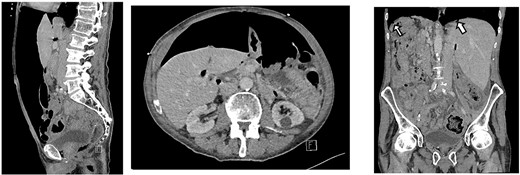

CT scan on initial presentation showing pneumoperitoneum without obvious cause. Sagittal, axial, coronal views. Arrows show pockets of free intraperitoneal air